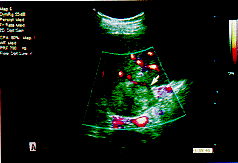

判定超声引导下微波治疗肝癌的效果:本组1例肝转移癌在第1次治疗前,进行能量谐波成像检查时发现肿瘤内和周边均可见明确的血流信号,特别是有三支滋养血流进入肿瘤内。在治疗后复查发现原肿瘤内和周边的血流信号明显减少,但仍见一支滋养血流存在。后经超声引导下穿刺活检证实肿瘤组织大部分坏死,但有残存的癌细胞;因此,在有血流信号的部位进行了第2次微波热凝固治疗。在第2次治疗后的能量谐波成像检查时,原肿瘤内和周围的血流信号完全消失,再行肿瘤的多点穿刺活检未发现任何存活癌细胞(图2)。

A.声像图显示肝右叶有一低回声肿瘤;B.能量多普勒超声显示少量肿瘤血流信号;C.注射超声造影剂后,能量二次谐波显示肿瘤周边和内部有丰富的血流信号;D.在第一次超声引导下微波治疗后48小时,复查能量二次谐波见肿瘤周边和内部血流信号明显减少。

图2 肝转移癌(箭头所示)